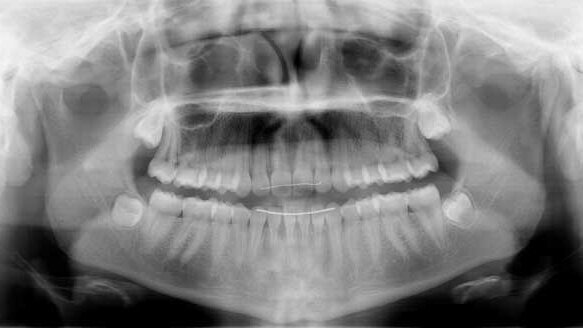

A 12½-year-old, healthy female patient presented, following referral by her pediatric dentist, with a concern for crowding and impacted permanent maxillary canines. In acknowledging the significant crowding, the parents and patient vocalized the desire to avoid permanent tooth extractions.

The examination and diagnostic records confirmed facially blocked maxillary canines, lateral incisor malalignment and maxillary first premolars erupting mesially into the canine space. All the maxillary and mandibular primary molars were present, and I noted that there was a significant size difference that would aid in spacing requirements for a non-extraction treatment plan.

In addition, the maxillary incisors were upright and the maxillary midline was shifted to the right, both of which would promote the ability to open canine spacing required. The molar relations were end-to-end.

After eight months of maxillary arch only treatment, all the space needed for teeth to erupt was present and the most mal-aligned maxillary right canine had erupted. Progress records were taken to evaluate incisor positioning, and it was determined that the initial goals of opening canine space and optimizing the incisor position without excessive transverse crown tipping or incisor proclination was successful.